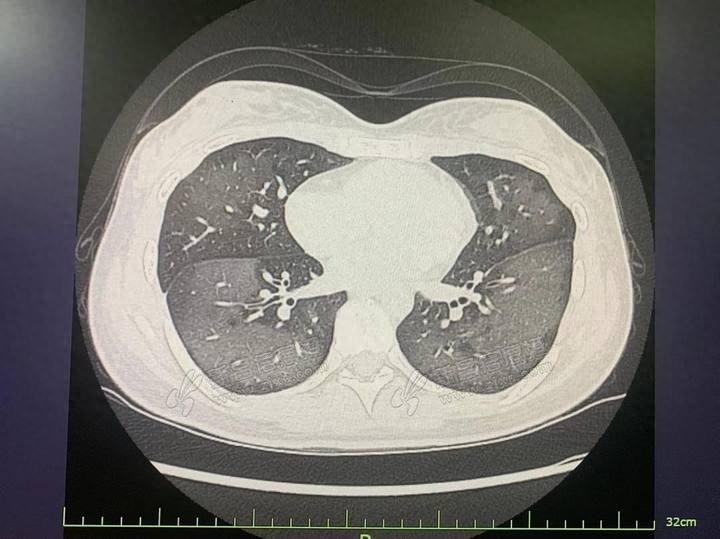

眼下很多人都在用!20岁绍兴姑娘查出“白肺”

夏天的太阳毒辣辣,讲究一点的出门时会往身上喷一喷防晒喷雾。但就是这款近年来热门的防晒产品,让20岁的姑娘得了急性过敏性肺炎。这是怎么回事呢?对着面部猛喷,姑娘“白肺”了6月17日中午,20岁的绍兴姑娘丽丽( ...